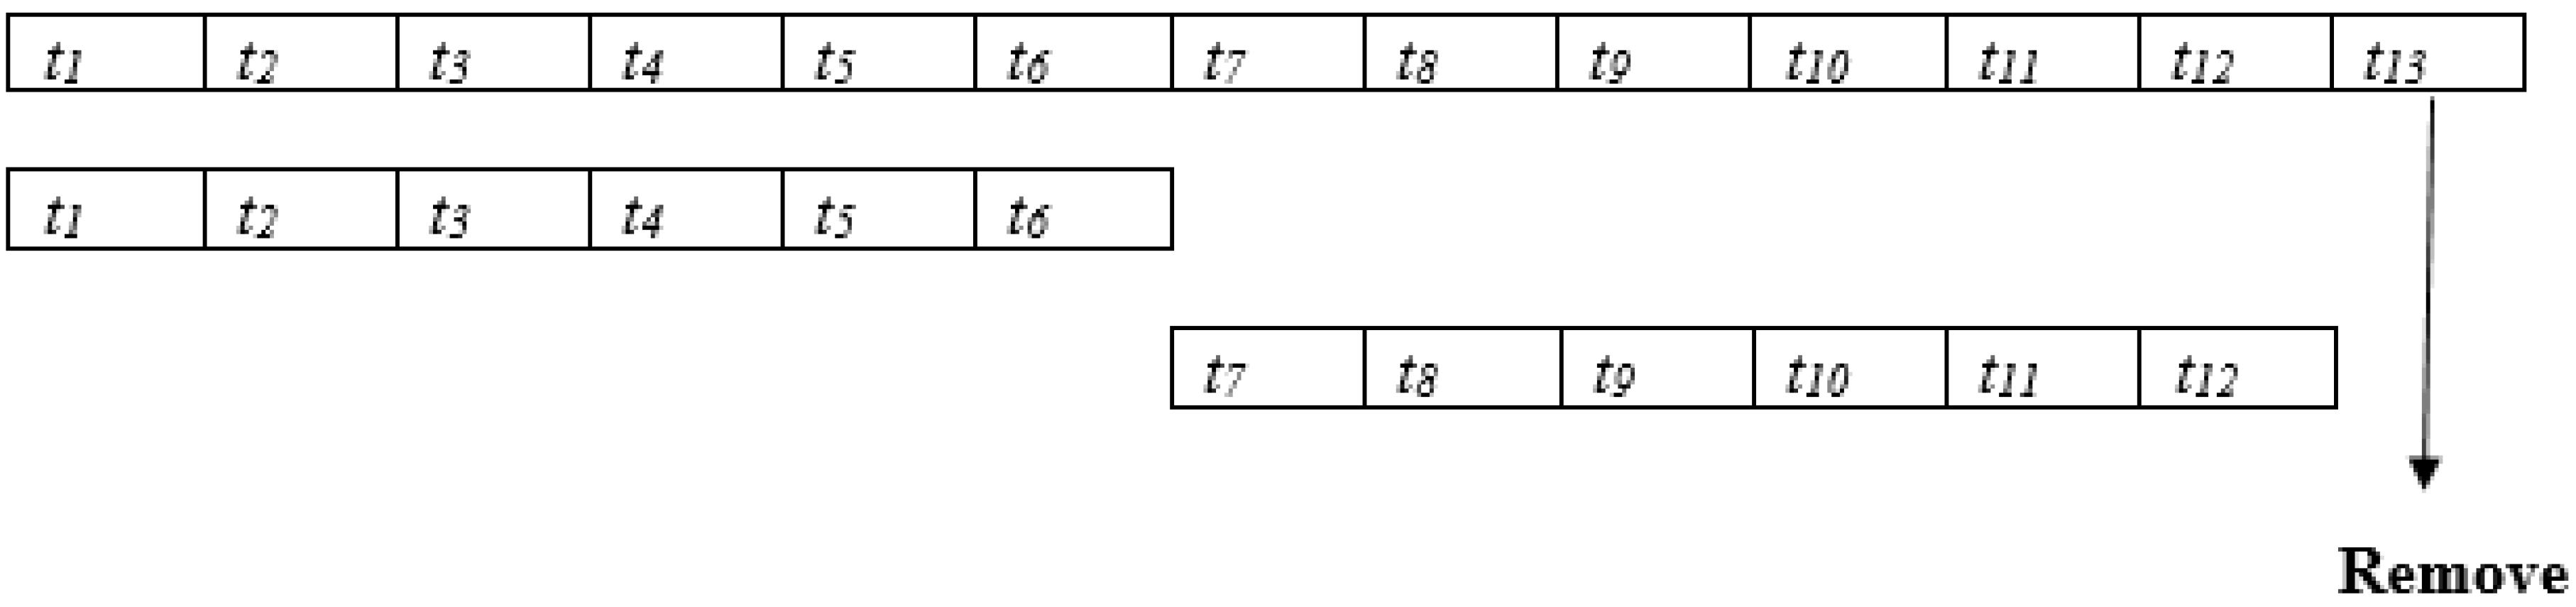

- The temporal representations of the ocular cases are taken in seven successive visual field tests over 4.3 years to test the progression of the disease and predict the progression using deep learning.

- Proposed Model and Experimental Results

3.1. Experimental Results Analyses

3.2. Experimental Results